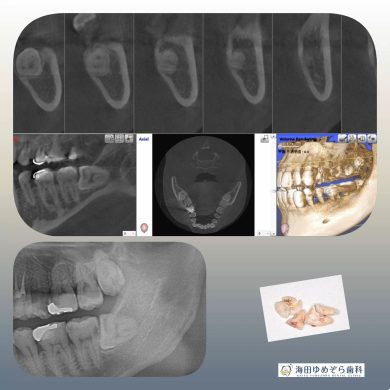

横向き親知らずの抜歯症例

院長はこのような横向きに埋まっている抜歯ケースも

1000症例以上の手術実績あり☆

横に埋まっている場合はCT撮影で安心です☆